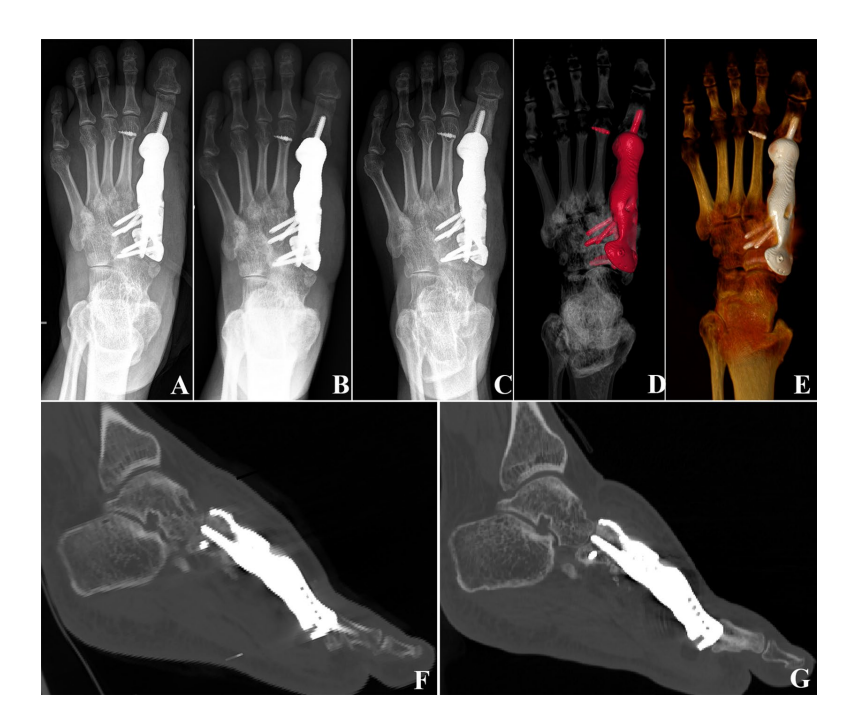

Clinical application research on the titanium metal metatarsal prosthesis designed through FEA and manufactured by 3D printing